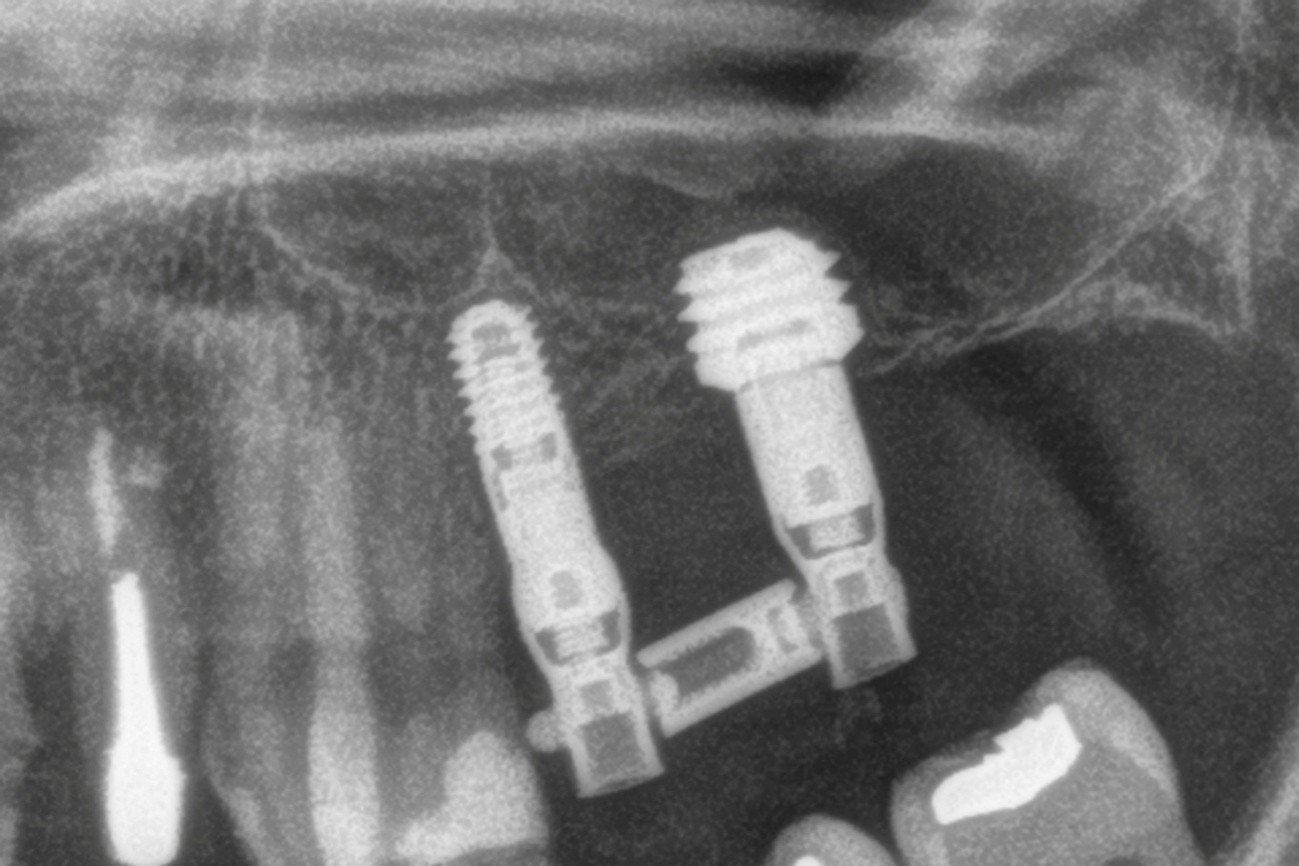

Métodos: Se llevó a cabo un caso clínico en una paciente de 40 años con fracaso de restauración fija dentosoportada en el incisivo central superior izquierdo, asociado a caries radicular subgingival con mal pronóstico restaurador. Tras la evaluación clínica y radiográfica, se indicó la exodoncia atraumática del diente afectado. Inmediatamente después, se realizó la colocación de un implante postextracción. El defecto periimplantario (gap) fue rellenado con un xenoinjerto óseo bovino. De forma simultánea, se llevó a cabo un injerto de tejido conectivo con el objetivo de optimizar el volumen y la estabilidad de los tejidos blandos periimplantarios. Se procedió a la colocación de una restauración provisional inmediata atornillada, diseñada para preservar el perfil de emergencia y guiar la cicatrización de los tejidos periimplantarios. Tras un periodo de cicatrización de cuatro meses, se colocó la restauración definitiva atornillada.

Resultados: El seguimiento clínico y radiológico evidenció una correcta osteointegración, estabilidad de los tejidos periimplantarios y un resultado estético satisfactorio, mantenido a los cuatro años.